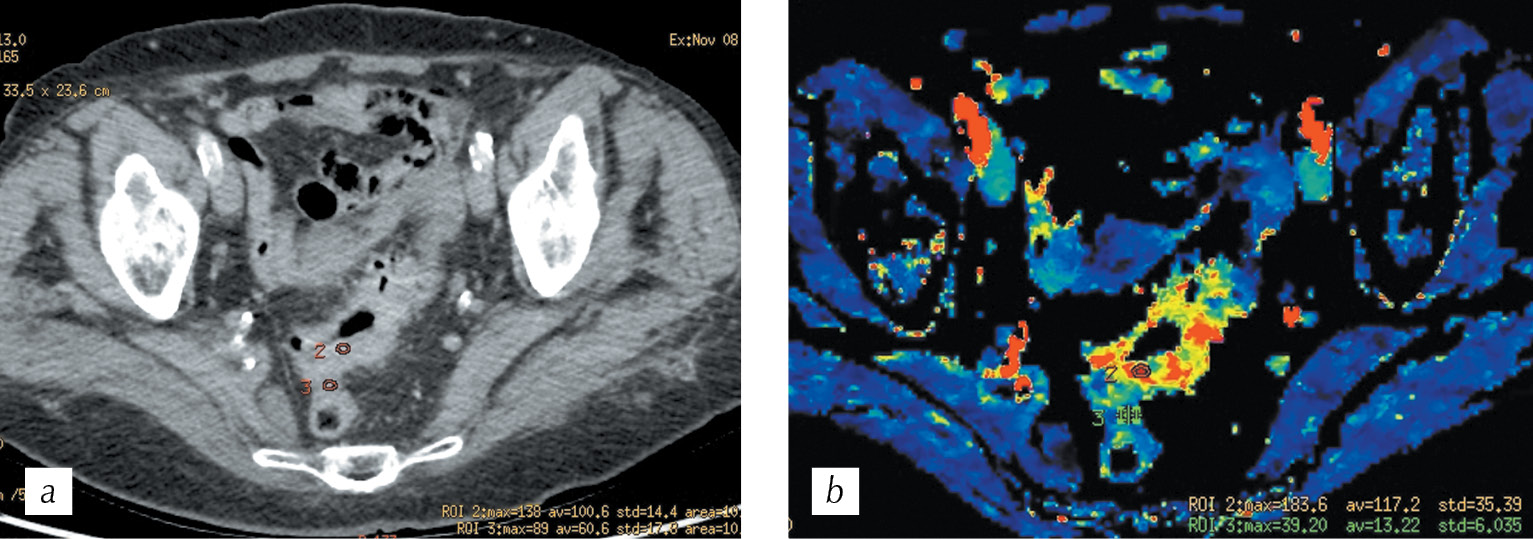

It was revealed that for a moderately differentiated adenocarcinoma, the visual assessment of the parametric cards is characterized by a clear difference between the tumor vascularization and the adjacent intact intestinal walls. Further, the boundaries of infiltrative changes in the intestinal wall during PCT were wider when compared to that obtained during standard spiral CT (Fig. 7, a, b). Following the placement of the ROI 2 labels in the tumor, and ROI 3 labels in the wall of the intact intestine, we obtained tables of digital values that demonstrate clear differences in the blood flow velocity indicator as BF in the tumor wall minand intact intestine was 112 ml/100g per min and 16 ml/100 g per min, respectively (Fig. 8, a). The density–time plot indicates functional changes in the tumor tissue in the form of the rise in curve 2 after 15 s of scanning, with a peak at 28 s and 3 s after the appearance of a peak in the afferent vessel. The green curve indicate that changes in the intact intestinal wall had a relatively straight course without significant peaks (Fig. 8, b).

Fig. 7. HCT, multiplanar reconstruction in the axial plane in the portal phase (a) and СT perfusion, parametric map of the blood flow (b) with ROI 2 in the invasive part of the tumor and ROI 3 in the intact intestinal walls

Рис. 7. Спиральная компьютерная томография, мультипланарная реконструкция в аксиальной плоскости в портальную фазу сканирования (a) и перфузионная компьютерная томография, цветная параметрическая карта скорости кровотока (b) с метками ROI 2 в инвазивной части опухоли и ROI 3 в смежных интактных стенках кишки

Fig. 8. Summary tables of perfusion parameters (а), the density-time graph (b) for the ROI 2 area in the tumor and ROI 3 in the intact intestinal wall

Рис. 8. Сводные таблицы числовых значений (a), график «плотность – время» (b) для меток ROI 2 в опухоли и ROI 3 в интактной стенке кишки

Fig. 10. HCT. Multiplanar reconstruction in the axial plane to the arterial phase (a) and CT perfusion, parametric map of blood volume (b) with ROI 2 marks in the most vascularized area and ROI 3 in the contralateral intestinal wall

Рис. 10. Спиральная компьютерная томография. Мультипланарная реконструкция в аксиальной плоскости в артериальную фазу сканирования (a) и перфузионная компьютерная томография, цветная параметрическая карта объема кровотока (b) с метками ROI 2 в наиболее васкуляризированном участке и ROI 3 в контралатеральной стенке кишки